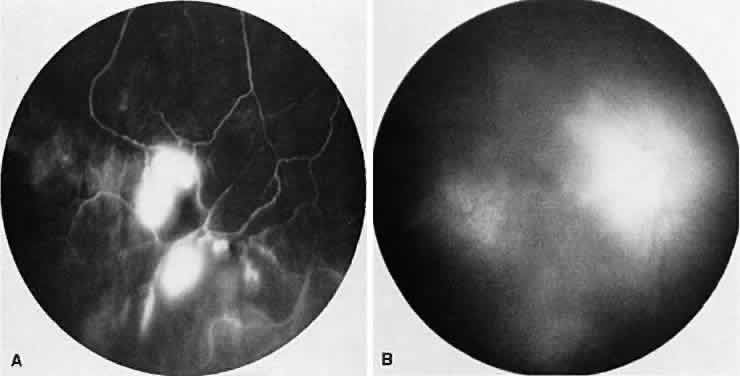

Fig. 8. Sarcoidosis. A. Fluorescein angiography shows two separate areas of neovascularization of the peripheral retina. B. Extreme leakage of dye from the right disc with cystoid macular edema of the right macular region in a patient with chronic sarcoidosis.

The FA reflects the various clinical entities. Retinal venular walls stain, particularly where there are perivenular exudates.25–27 More extensive venous involvement can produce a picture of dilated veins and perivenous leakage.27 Peripheral neovascularization occurs near areas of retinal capillary nonperfusion.25,28 Optic disc granulomas and optic disc neovascularization both leak extensively (Fig. 8A); sarcoid retinal lesions also stain (see Fig. 7B).27 In disc edema, the disc is hyperfluorescent and leaks fluorescein (see Fig. 8B).25

Four main patterns can be identified with ICG angiography. The first and most common pattern is hypofluorescent dark spots in the early and intermediate phases of the angiogram. These spots either become isofluorescent or remain hypofluorescent in the late phases. The second pattern is focal hyperfluorescent spots seen in the intermediate and late phases. The third pattern is fuzzy choroidal vessels due to perivascular choroidal leakage in the intermediate phase. Finally, the fourth pattern is characterized by diffuse zonal hyperfluorescence representing choroidal staining in the late phase of the angiogram. The latter two patterns resolved after systemic corticosteroid treatment.29